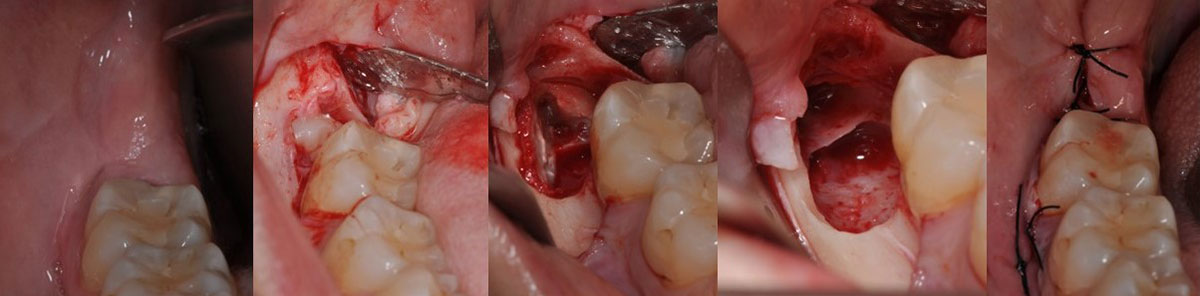

Entre las intervenciones que se realizan con mayor frecuencia se encuentran las extracciones de cordales incluidos (muelas del juicio), caninos incluidos y otros dientes retenidos, tratamiento de frenillos bucales, tomas de biopsias, regeneraciones óseas e injertos de encía.